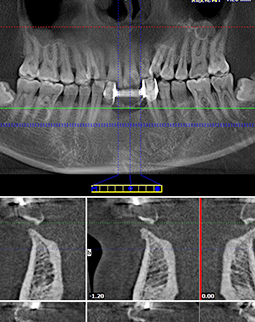

这是我种牙后的第二天,麻药退去了,还是有些不舒服,昨天种完牙一直咬了40分钟左右的棉球,现在还是有点渗血,多少有点疼,客服刚给我致电,告诉我不要吐口水,不然会加重出血量。昨天种好牙到现在,我吃了两餐饭了,然后漱了下口,我告诉你们,种完牙不能马上就刷牙。距离昨天手术过去了24小时,我到现在创口没有肿胀,现在就希望快点愈合。有人担心“种植牙有危险,种植牙会出很多血,种植牙创口会很大”,我问医生要了我的CT和种牙口内照,想给大家看一下。

左边是我种牙之前,缺牙很久了,所以这个牙床口长好了。右边是我的种植牙创口,大小和牙根差不多,这个很容易理解,因为种植体就是人造牙根,得有个洞才能把它埋进去,我种牙的创口很小了,基本是微创的,比起过去的切开牙龈种牙好太多了!所以大家不用太担心,你选个好的医院和医生,种植牙还是很靠谱的。